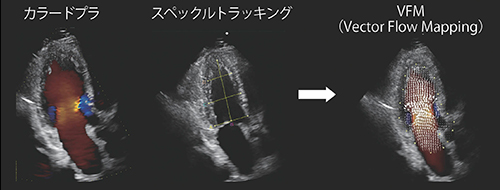

“Vector Flow Mapping(以下,VFM)”は,血流をベクトル表示によって可視化する技術であり10),血流の効率性や相対圧イメージングが可能である。2020年に発表された米国での研究11)では,心不全患者の重症度に応じた超音波指標の診断精度について人工知能を用いて検証したところ,駆出率(EF)やGlobal Longitudinal Strain(GLS)を抑えて,VFM指標が最重要指標として挙げられた。また,この研究では,超音波指標にVFM指標を加えることにより,心不全重症度分類の正確性が向上すると報告されている。以後,VFM指標について紹介する。

VFMでは,カラードプラ画像を取得することにより,カラードプラによる血流速度情報と2D画像のトラッキング技術による壁運動情報を用いて,容易に心臓・血管内腔の速度ベクトル分布を得ることができ(図3),さまざまな研究により精度,再現性が検証ずみである12)〜14)。

図3 VFMの原理